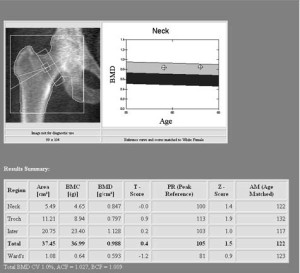

Важно понимать, что в результате такого анализа проводится измерение не самой минеральной плотности костной ткани. Оцениваются Z и Т-критерии. То есть существуют определенные нормы, отклонение от которых считается определенной стадией остеопороза.

Под Т-критерием понимается количество стандартных отклонений ниже и выше среднего показателя массы костей у молодых женщин в возрастной категории от 30 до 35 лет. Когда увеличивается возраст, в норме снижается и костная масса, поэтому критерий тоже уменьшается.

Под Z-критерием понимается число стандартных отклонений, находящихся ниже или выше среднего показателя, но уже у пациентов средневозрастной нормы. Этот критерий позволяет учитывать даже снижение костной плотности в пределах нормы, которое происходит с возрастом.

Отсутствие или наличие остеопороза, как и степень его выраженности, определяются по Т-критерию. Оценку минеральной плотности костной ткани советуется проводить один раз в год, особенно при наличии факторов риска.

Если рассматривать возможные показатели анализов, то есть те, которые находятся в пределах нормы и те, которые говорят о наличии заболеваний. Хорошие показатели – не больше -1 стандартного отклонения от костной пиковой массы по Т-критерию. Если развивается остеопения, в зависимости от ее степени результаты будет не более -2,5. При остеопорозе показатели больше той цифры.